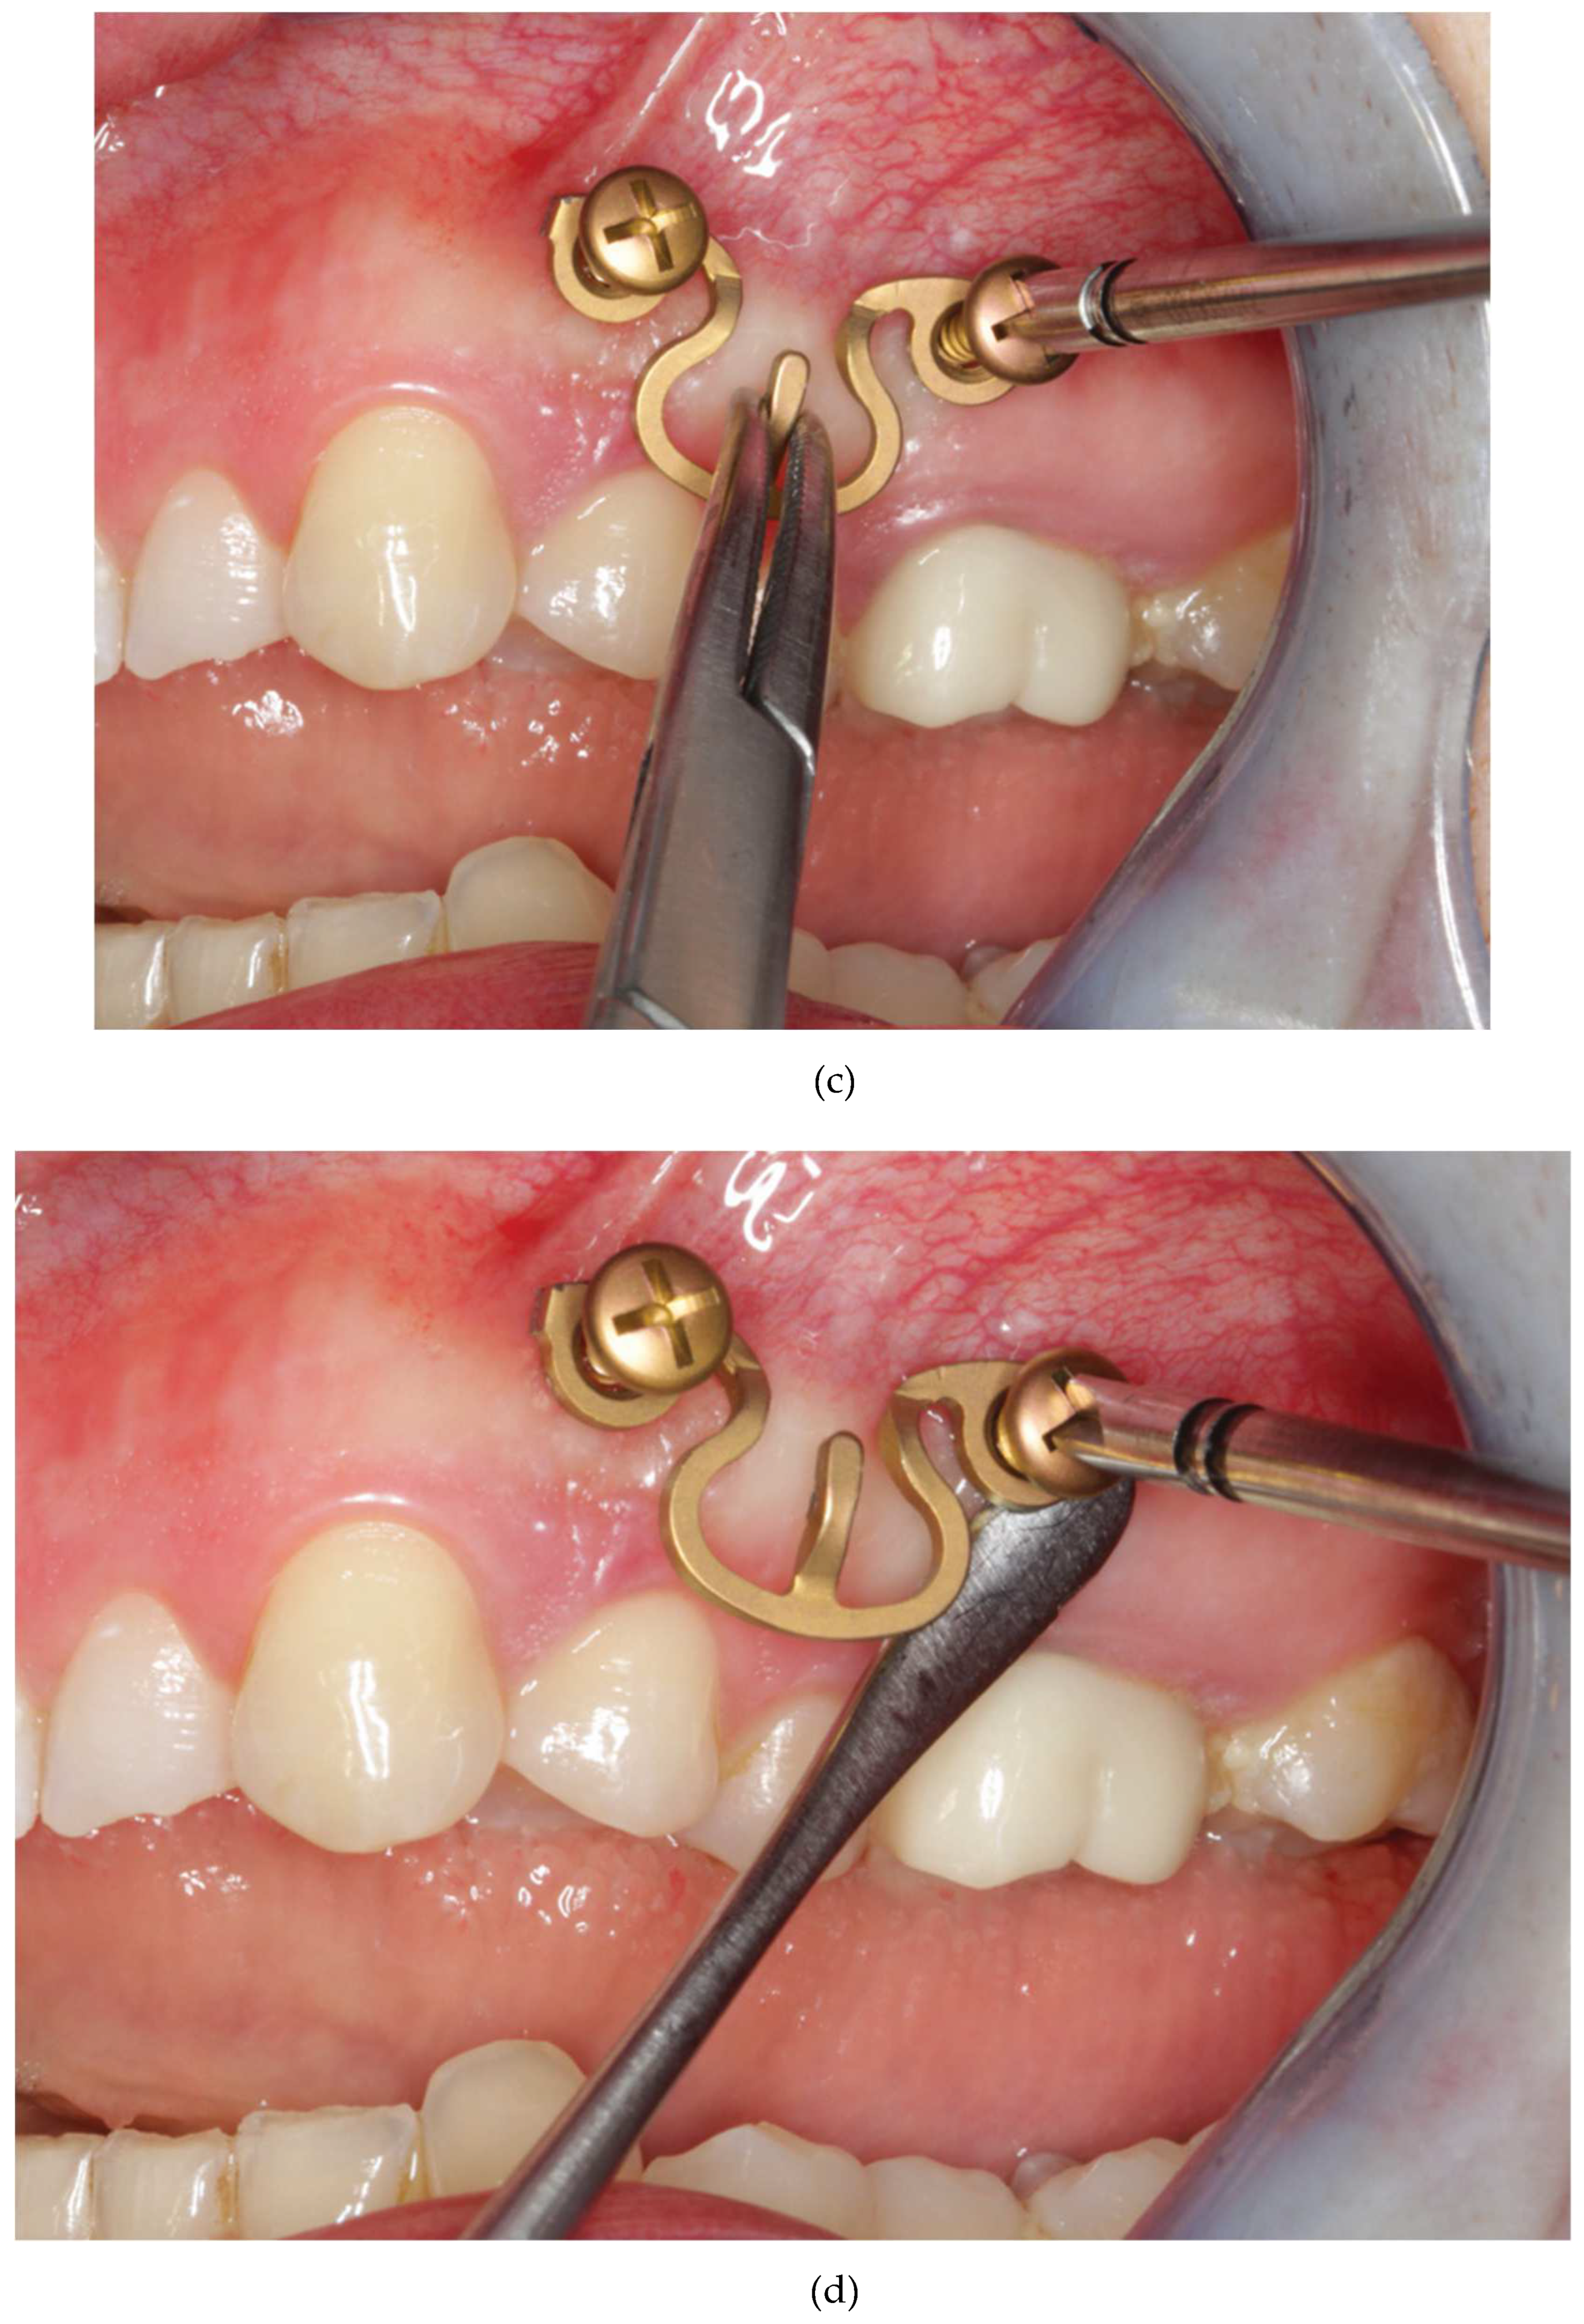

Figure 16.

Figure 16 A: Case with a double mandibular fracture – right mandibular angle; left condylar base (see panoramic x-ray in

Figure 16 L ). Deep bite not suitable for conventional tooth borne arch bars. A low profile MWP Omega segment is tried on along the mucogingival transition zone for interradicular screw fixation in the premolar region of the left maxilla. Interferences with the habitual occlusal position and / or articulatory movements must be ruled out.

Figure 16 B: Owing to the more comfortable access the anterior screw is inserted first. Angulation of the screw should be avoided. The conical locking head of the screw should not get engaged into the plate hole prematurely.

Figure 16 C: The posterior screw is turned likewise halfway into the bone for a loose prefixation of the MWP segment.

Figure 16 D: The MWP segment is supported with a Freer elevator as a spacer below the flatbed portion and the screws are tightened alternately until the plate segment is firmly gripped by the locking threads.

Figure 16 E: Screw fixation of MWP segment completed. Most of the time the conical locking head cannot be fully countersunk in the plate hole. It is essential, however, that the threads of the plate hole and the locking threads of the screw effectively purchase.

Figure 16 F: High profile MWP Omega segment adapted to the interradicular spaces in the premolar region of the opposite jaw, in this case the left mandible. Interferences with the habitual occlusal position and / or articulatory movements must be ruled out.

Figure 16 G: Prefixation – plate segment still moveable.

Figure 16 H: Posterior screw turned into the plate hole, supporting the plate with a Freer elevator from underneath.

Figure 16 I: Anterior screw turned in, while plate segment is supported with Freer elevator - alternate tightening of the screws.

Figure 16 J: MWP segment finally fixed in juxtaposition to the vestibular tooth crowns just below occlusal plane. A steep canine guidance, however, averts disruptive contacts between the second upper premolar and the top rail of the plate.

Figure 16 K: MWP Omega segments mounted in all jaw quadrants for temporary intraoperative MMF with wire ligatures to immobilize the mandible. Note: Conical locking heads are partially countersunk, only.

Figure 16 L: Postoperative Panoramic x-ray after transoral ORIF (miniplate osteosynthesis). 4 MWP segments left in place for optional functional treatment during follow-up. All screws for MWP attachment located in interradicular alveolar bone Inset: four MWP Omega segments as oriented and used in this illustrative case.

Source/origin of Figure 16 A – L : Photograph collection – C.P. Cornelius